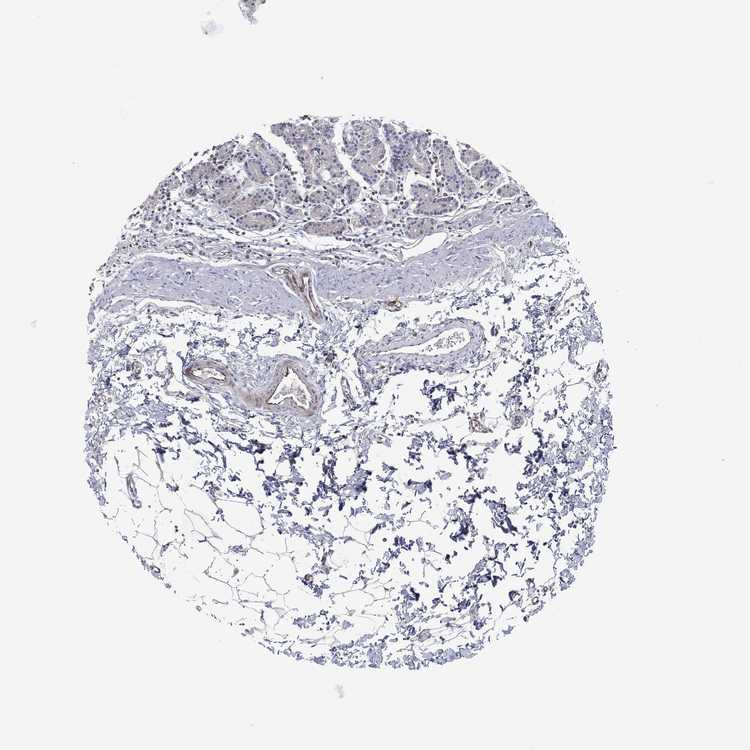

STOMACH 1 - Antibody stainingi

Antibody staining in the annotated cell types in the current human tissue is reported as not detected, low, medium, or high, based on conventional immunohistochemistry profiling in selected tissues. This score is based on the combination of the staining intensity and fraction of stained cells.

Each image is clickable and will lead to virtual microscopy that enables deeper exploration of all samples and also displays staining intensity scores, fraction scores and subcellular localization as well as patient and tissue information for each sample.

Antibody HPA065030

Glandular cells Not detected